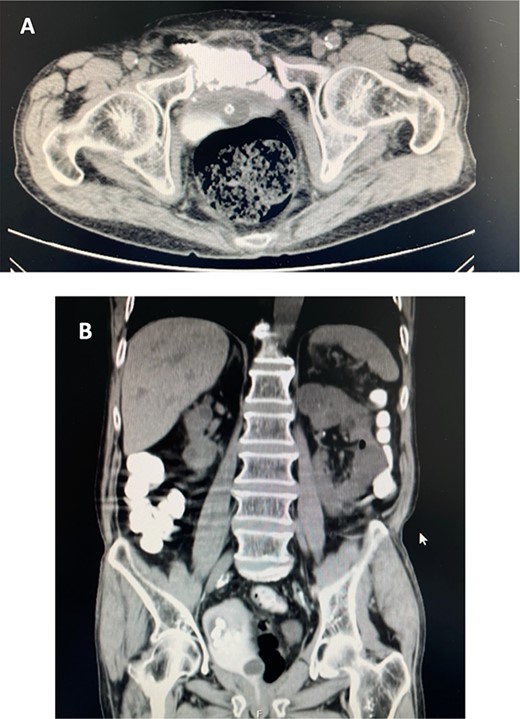

After surgery, the patient presented an elevated post voiding volume and recurrent urinary tract infections with kidney function impairment and was proposed to self-catheterization. In 2017, the patient developed faecaluria. At this time, a cystoscopy was done and multiple neobladder stones were visible but no stenosis or fistulas were identified. CT scan with oral contrast revealed passage of contrast from an ileal loop to neobladder (Fig. 1a) and multiple neobladder stones (Fig. 1b) making the diagnosis of ileal to neobladder fistula. A first conservative treatment with low-residue diet and prolonged transurethral urine drainage was attempted but the fistula did not close, and the patient maintained faecaluria. We proposed the patient for minimally invasive laparoscopic repair of the fistula and removal of the stones. The pre-operative serum creatinine was 2.7 mg/dL with a glomerular filtration rate of 21.75 mL/min. Urine analysis revealed an Escherichia coli susceptible to amoxicillin–clavulanic and cotrimoxazole but resistant to cephalosporins. Antibiotic prophylaxis with 1.2 g of amoxicillin-clavulanic was administered to the patient. Preoperative bowel preparation was not done.

(A). CT scan with oral contrast (axial view) revealed passage of contrast from an ileal loop to neobladder. (B). CT scan with oral contrast (coronal view) showing multiple stones in neobladder.